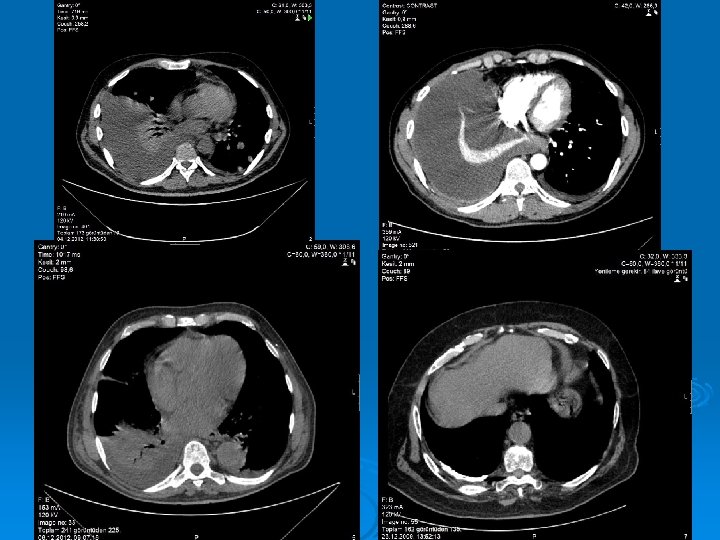

Radiology The fluid initially accumulates in the more dependent recesses of the thoracic cavity forming a Damoiseau Line Ø 200 -300 ml of pleural effusion can be detected on standard chest radiograph as blunting of the costophrenic angle Ø

Massive pleural fluid often shifts the mediastinum to the opposite side

Accumulation of the fluid between the diaphragm and the interior surface of the lung (Subpulmonic fluid): The hemidiaphragm appears to be elevated (Widening the distance between the top of the gastric bubble and the top of the left hemidiaphragm (>2 cm) and flatened Blunting of the posterior costophrenic angle on the lateral chest radiograph

Ø Ultrasound is able to demonstrate smaller amounts of fluid as 100 ml Ø CT has similar sensitivity to ultrasound, not routine but can be performed to evaluate concomitant paranchymal lesions Ø CT is sensitive in identifying pleural thickening and calcification